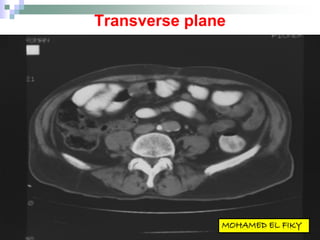

Transverse plane

 The horizontal plane

dividing the body

into upper and lower

portions

 Also called the

Horizontal plane